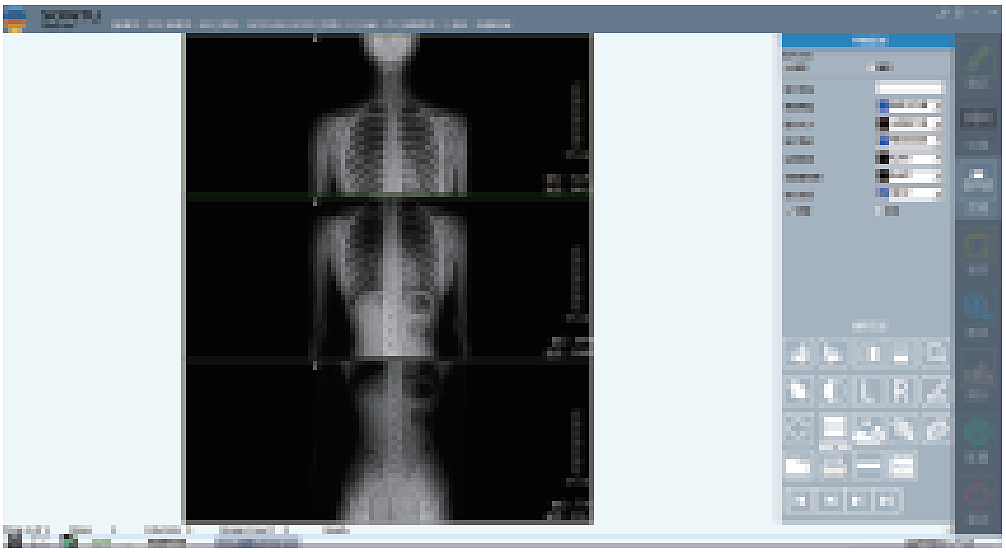

深图软件操作系统:

一键即可完成辅助诊断,定位可疑病变

深图AI辅助诊断系统标注示意:

标注异常位置、呈现病变信息